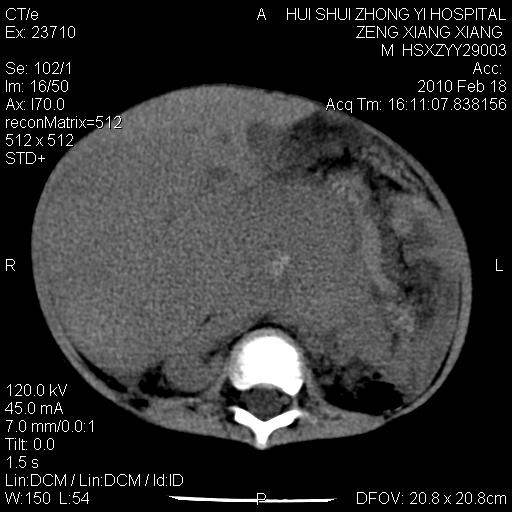

标题: PED3106:男,2岁,腹胀1月。 [打印本页]

标题: PED3106:男,2岁,腹胀1月。

定位腹膜后,肾上腺来源;

定性:恶性神经源性,肾上腺神经节母细胞瘤可能性大。

鉴别:肝母、肾母、肝脏中胚层错构瘤。

依据:年龄、有钙化,肾脏及肝脏受压移位。

肝母细胞瘤可能性大,右肾形态大体可见,不支持肾母细胞瘤,右肾移位不明显,肾上腺神经母细胞瘤可能性不大。